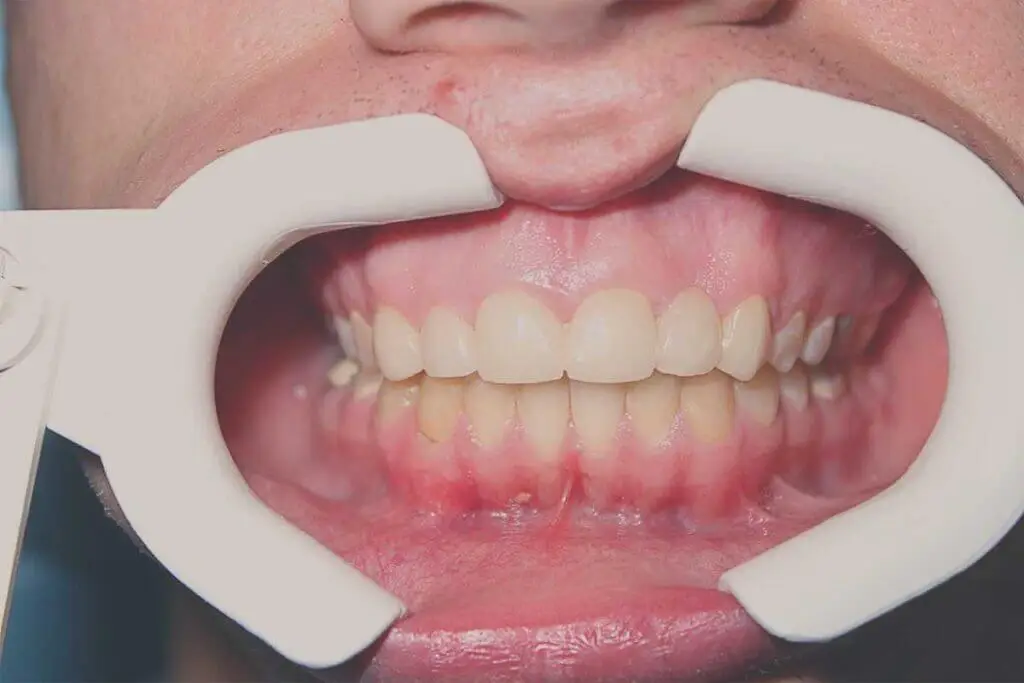

Cirkonkerámia korona

Páciensünk elégedetlen volt a felső frontfogainak régi pótlásával és fogainak esztétikai állapotával.

Dr. Bakonyi Panna az állapotfelmérést követően a felső régi fémkerámia pótlás cseréjét javasolta cirkonkerámiára. Az alsó jobb oldali foghiányra, illetve a nagymértékben sérült fogakra szintén cirkónium koronák készültek.

A többi fogtól jelentősen eltérő színű szemfogak fehérítése után értük el a tökéletes esztétikai eredményt.